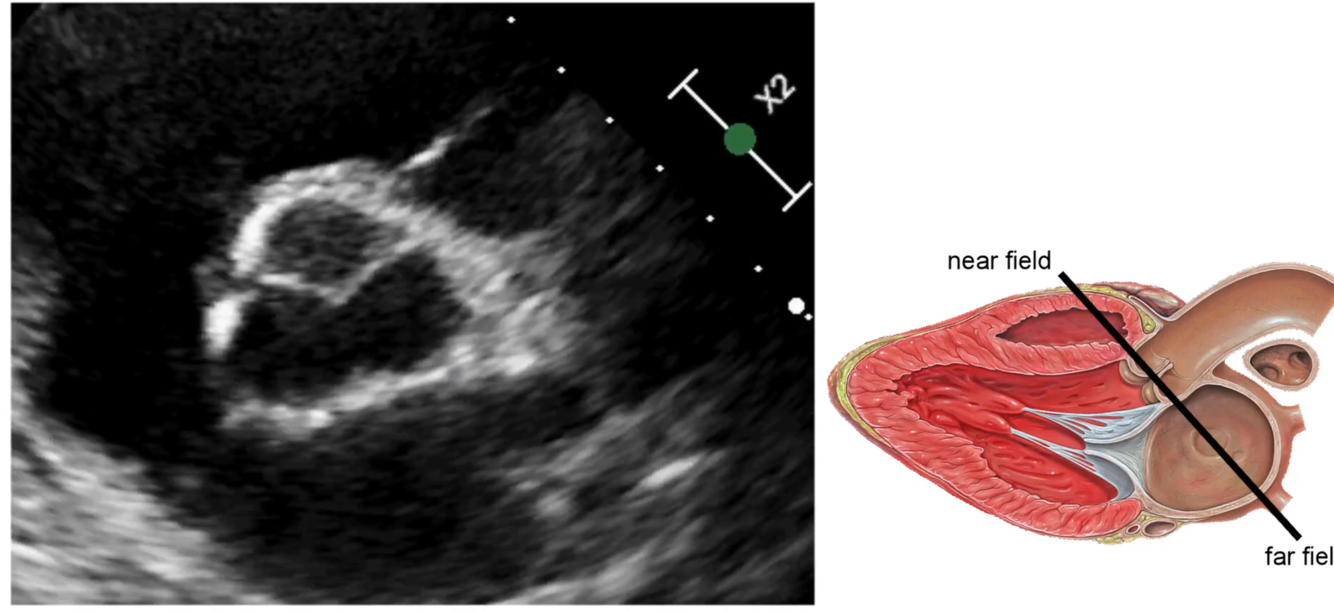

What are the name of the aortic valve cusps?